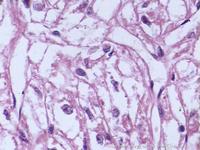

內鏡下大腸脂肪瘤呈黃色質軟的圓形狀腫塊。較大的黏膜下脂肪瘤常常突入腸腔,部分成為有蒂。活檢時有時可見黃色物流出。病理可見成熟的脂肪細胞和纖維性間質出確診。X線表現為光滑的腸腔內有蒂或廣基腫塊,具有形態不穩定的特徵,充盈缺損可以在鋇劑灌腸時隨外壓或排空而改變形態。